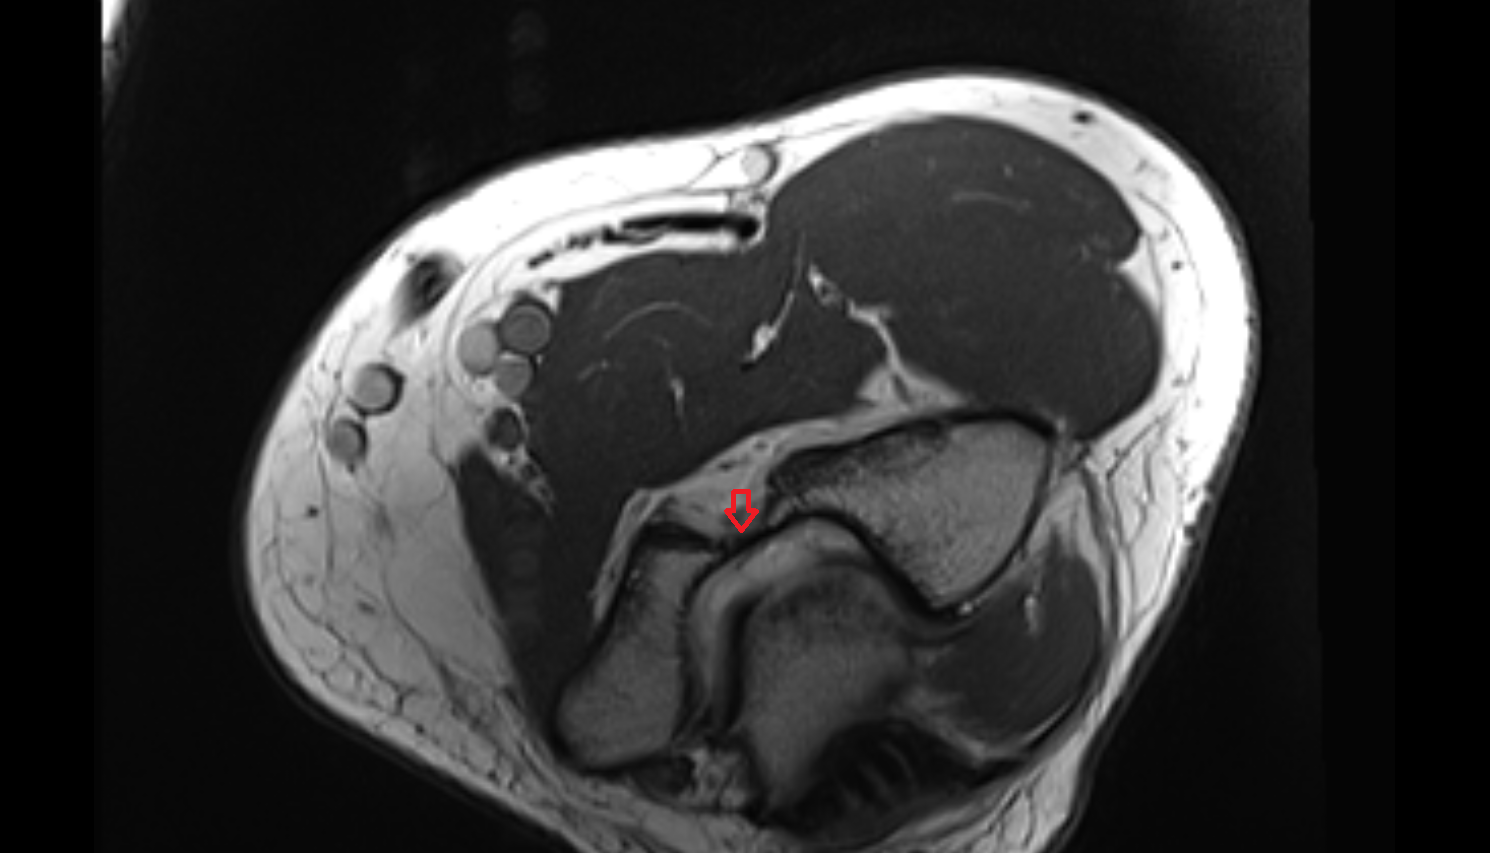

- Medial meniscus

- Lateral meniscus

- Knee Joint